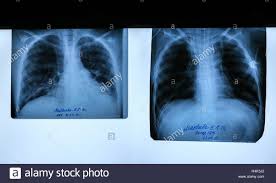

Fruhdiagnose Und Therapiekontrolle Bei Mukoviszidose

Fruhdiagnose Und Therapiekontrolle Bei Mukoviszidose from www.mta-dialog.de